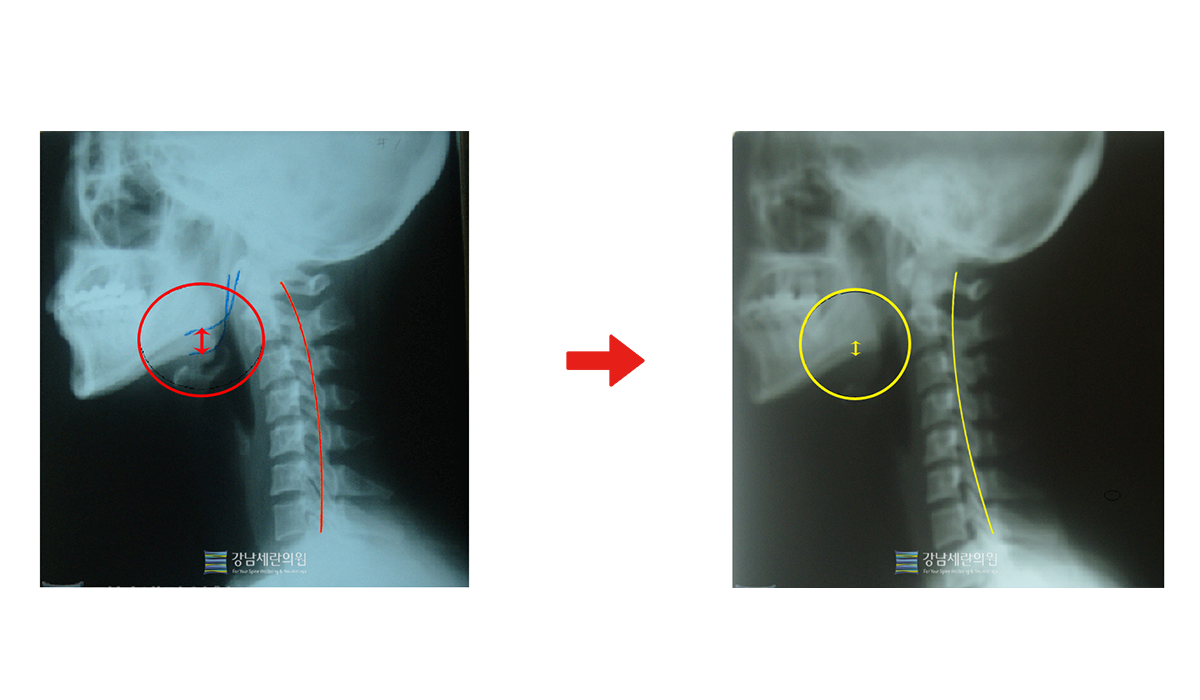

일자목 치료 전 ▶ 일자목 30회(3개월) 치료 후